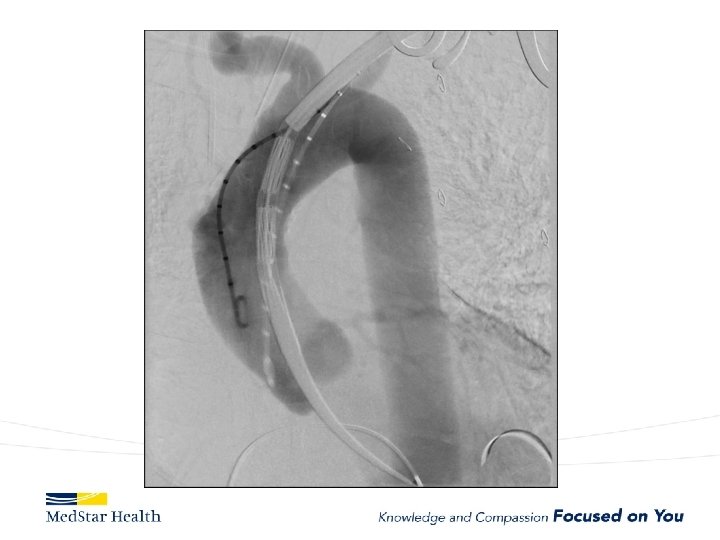

Ascending Aorta • Currently off label unless in IDE • Challenges – Devices too long or too small for ascending – More complex terrain • Entire cardiac output • Valve/coronaries below • Inomminate above. – New Commercial Devices now available (shorter/tapered)

Current experience with ascending TEVAR JTCVS 2017 Nov 22, Roselli et al. 2006 to 2016 39 patients very high risk for open surgery – A dissection (12, 31%), – intramural hematoma (2, 5%), – pseudoaneurysm (22, 56%), – chronic dissection suture line entry tear (3, 8%). TEVAR in 36 Operative mortality 13%; 5 deaths all in Type A dissections Other complications: – stroke in 4 patients (10%), myocardial infarction in 2 patients (5%), tracheostomy in 2 patients (5%), and dialysis in 2 patients (5%).

• 30 days, 1 year, and 5 years overall survival: – 81%, 74%, and 64% • Freedom from reintervention: – 85%, 77%, and 68% • Significantly higher hazard of mortality with; – zone 0 A versus 0 C (P =. 020) – older age (P =. 026)

Type A Dissection

ARCH